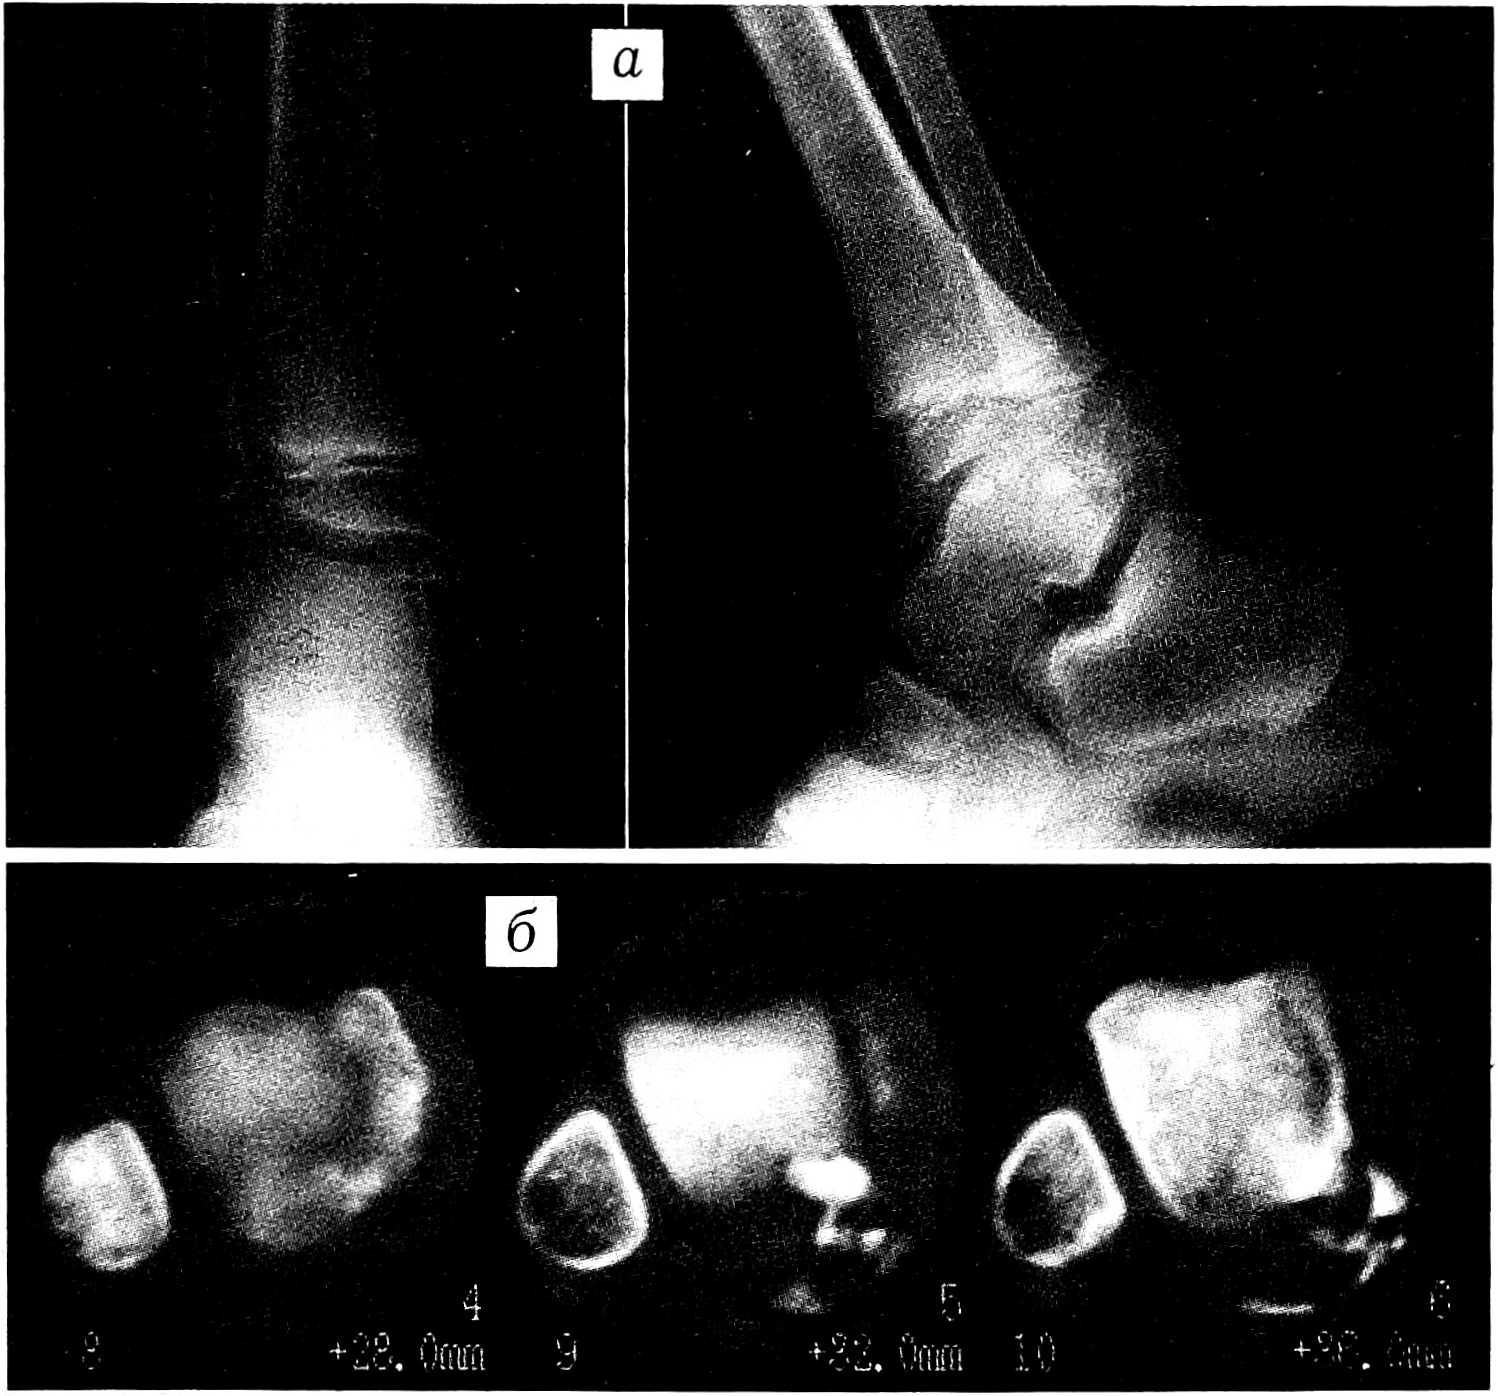

Рентгенологически, как правило, выявлялась асимметрия эпифиза: пораженная половина его была массивной, увеличенной в объеме, причудливо деформированной, имела неоднородную структуру с участками обызвествления. В ряде случаев обнаруживались свободно лежащие внутрисуставные тела. Последнее время в диагностике ГЭД мы используем компьютерную томографию, которая позволяет, помимо структурных изменений пораженной кости, определить взаимоотношение патологических и здоровых тканей (рис. 1).

Рис. 1. Больной 6 лет с гемимелической эпифизарной дисплазией таранной кости.

a — рентгенограммы голеностопного сустава в прямой и боковой проекции; б — компьютерная томограмма.

При поступлении ось правой нижней конечности нарушена за счет стойкой болевой контрактуры в коленном суставе под углом 90°. Контуры сустава сглажены, сустав резко увеличен в объеме, деформирован. Кожные покровы над ним гиперемированные, лоснящиеся, теплее, чем на здоровой стороне. Движения в суставе отсутствуют. На уровне нижней трети правого бедра определяются патологическая подвижность, крепитация. Сосудистых и неврологических расстройств в правой нижней конечности не выявлено. На рентгенограммах обнаружен винтообразный перелом нижней трети правой бедренной кости со смещением отломков. Наружные мыщелки бедра и большеберцовой кости значительно увеличены, причудливо деформированы, неоднородной структуры, с участками обызвествления. Зоны роста нитевидные, местами закрытые (рис. 2, а). Нарушений со стороны внутренних органов не выявлено. Анализы крови и мочи в пределах возрастной нормы.

Рис. 2. Больной С. 13 лет с гемимелической эпифизарной дисплазией дистального эпифиза большеберцовой кости.

а — рентгенограммы коленного сустава в прямой и боковой проекции при поступлении: виден перелом нижней трети бедренной кости; б — патологические разрастания пораженных эпифизов (во время операции); в — рентгенограммы коленного сустава через 5 мес после операции.

Через 2 мес перелом сросся, и 14.04.97 было произведено хирургическое вмешательство. Во время операции обнаружены костно-хрящевые разрастания, исходящие из дистального эпифиза бедренной и проксимального эпифиза большеберцовой кости, размером 4×6 и 5×7 см, резко деформирующие суставные поверхности (рис. 2, б). Надколенник не был изменен, под ним в проекции межмыщелкового возвышения находилось свободно лежащее округлое костно-хрящевое образование диаметром 3 см. Произведены резекция коленного сустава, удаление патологических тканей, артродез с использованием кортикальных аллотрансплантатов.

Послеоперационный период протекал без осложнений, рана зажила первичным натяжением. Гипсовая иммобилизация продолжалась 5 мес. Контрольный осмотр: артродез состоялся (рис. 2, в), однако имеется укорочение правой ноги на 5 см, что требует дальнейшей ортопедической коррекции. Наблюдение за больным продолжается.

Приведенный нами случай тяжелого поражения коленного сустава у 13-летнего ребенка с ГЭД как нельзя лучше показывает актуальность проблемы своевременной диагностики и адекватного лечения этого заболевания. Современные методы лучевого исследования (компьютерная, магнитно-резонансная томография) имеют особую ценность для топической диагностики очага поражения, помогают хирургу выбрать адекватный, порой нестандартный метод оперативного вмешательства [10-12].